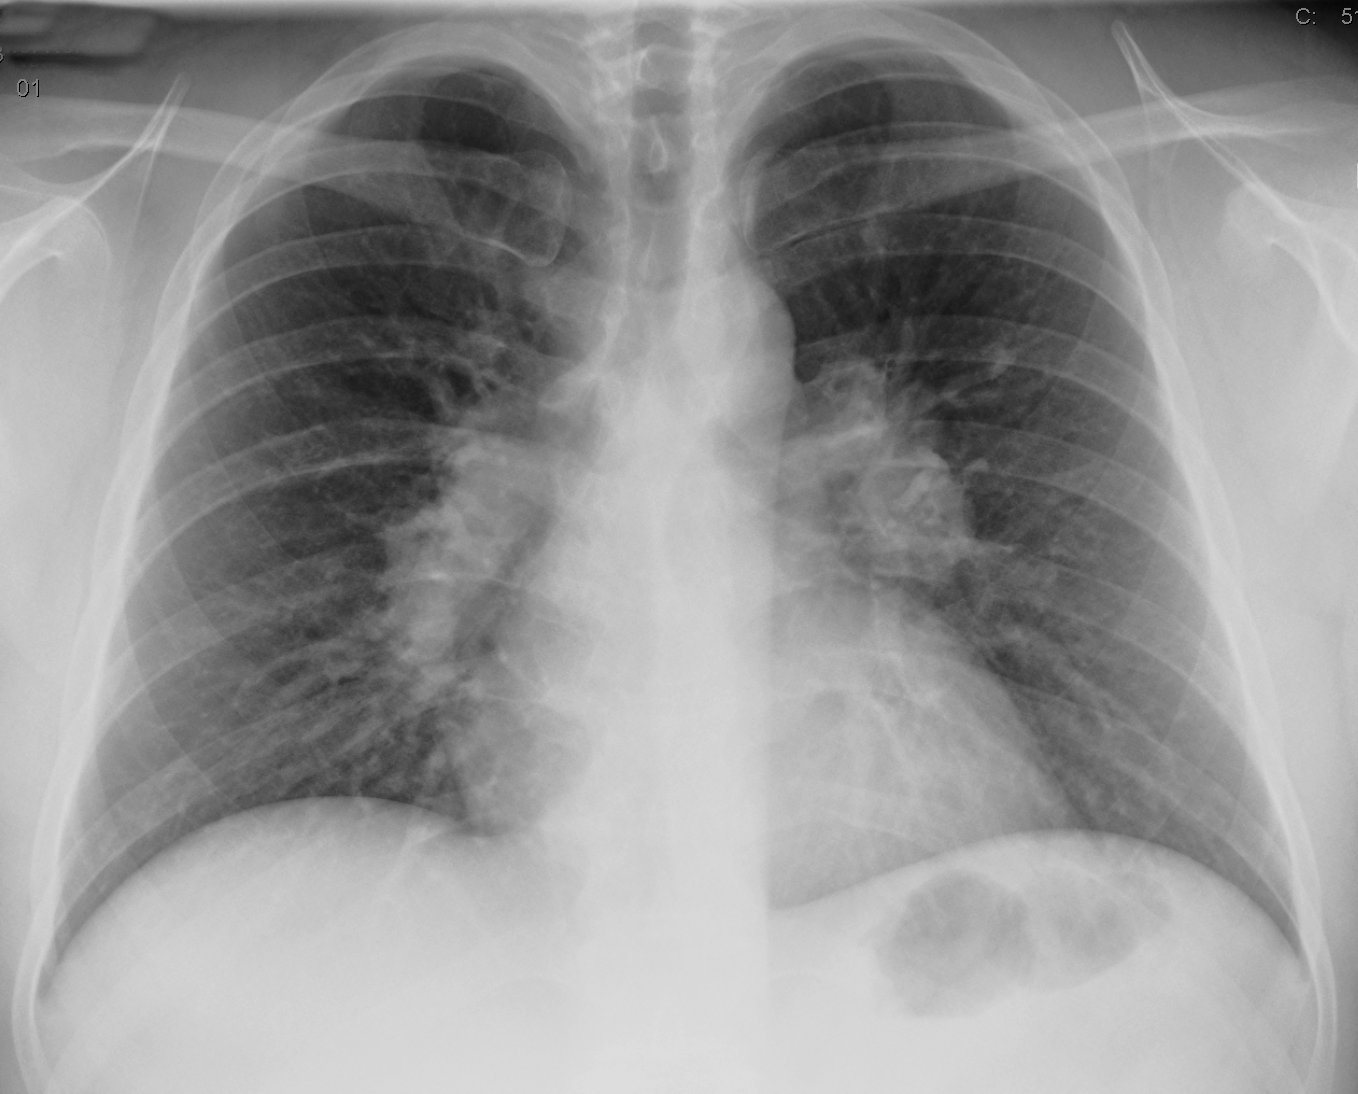

Инструментальные методы исследования, которые используют для подтверждения диагноза саркоидоза легких, это:

- рентгеноскопия и –графия органов грудной клетки – рентгенологические признаки изменений в легких определяются уже на первой и второй стадиях заболевания (зачастую бессимптомных);

Характер изменений в легких, выявленных во время рентгеноскопии и –графии органов грудной клетки, зависит от стадии заболевания:

- на первой стадии четко видно, что увеличились внутригрудные лимфатические узлы;

- на второй стадии, кроме увеличенных лимфоузлов, определяются темные очаги – гранулемы, которые могут сливаться между собой, а также признаки того, что легкое начинает прорастать соединительной тканью. На этой стадии фиброзом зачастую затронуты средние и нижние отделы легких – изменения легочной ткани нужно искать именно там, подозревая саркоидоз легких;

- на третьей стадии определяется существенное прорастание легкого соединительной тканью, массивное слияние гранулем, эмфизема (участки раздутой воздухом легочной ткани), нередко с ничем не заполненными полостями в легких, а также уплотнение плевры;

- четвертая стадия манифестируется тотальным разрастанием соединительной ткани в легких.